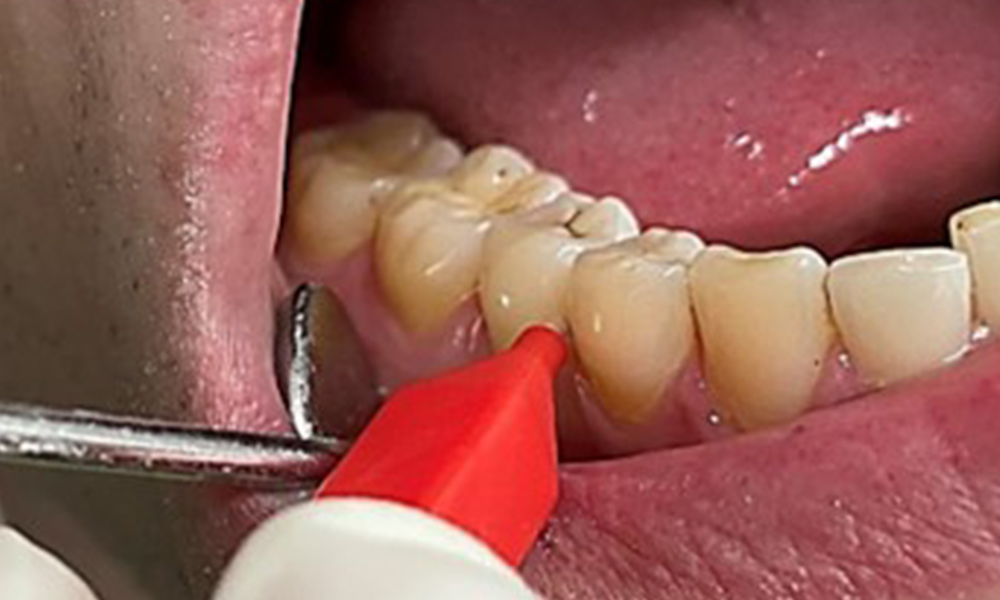

En raison d'un état de santé général par ailleurs favorable, les besoins déterminés lors de l'examen intra-oral seront déterminants pour le traitement. Il sera essentiel de déterminer périodiquement les profondeurs de sondage. Le saignement gingival diminue chez les fumeurs, c'est pourquoi le diagnostic clinique de la parodontite ne peut se faire que par sondage (Fig. 7). En se concentrant exclusivement sur la détermination des indices de saignement, on risque d'occulter une parodontite ou une gingivite existante. (5)